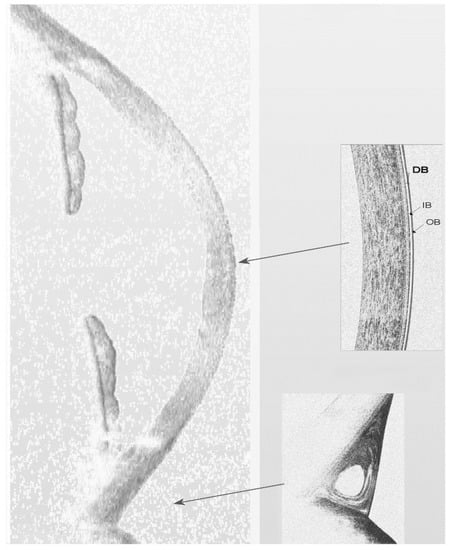

5. Tear Meniscus

6.1. Cornea

6.3. Meibomian Glands